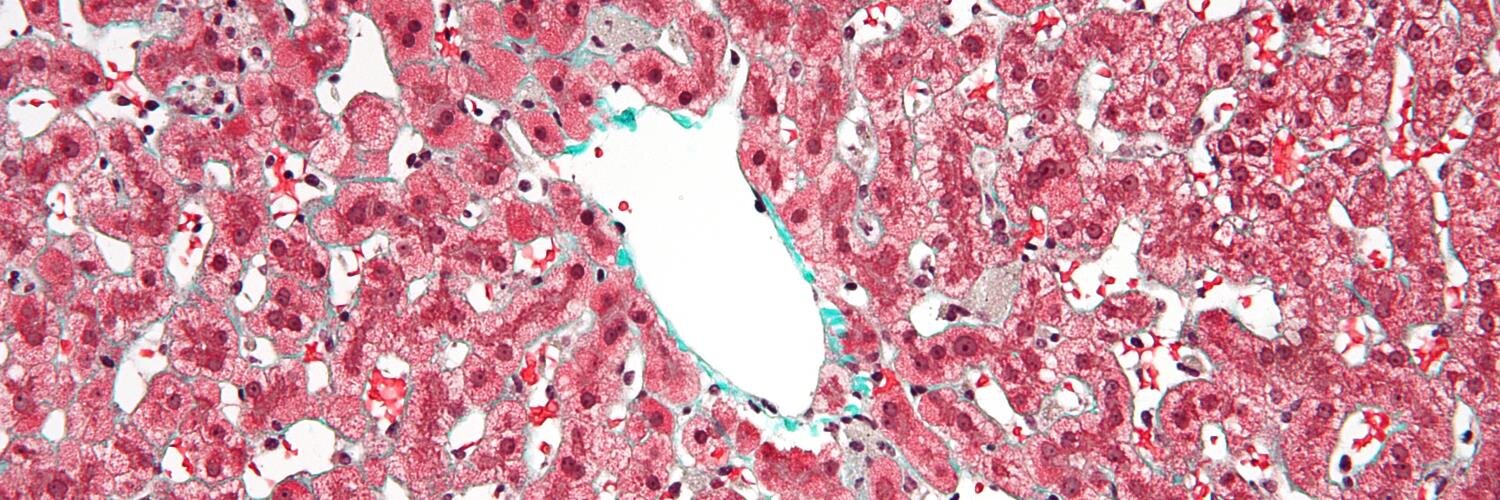

Kevork Peltekian, MD

Dr. Peltekian, is a hepatologist with the Division of Digestive Care & Endoscopy advocating for Atlantic Canadians with liver disease.